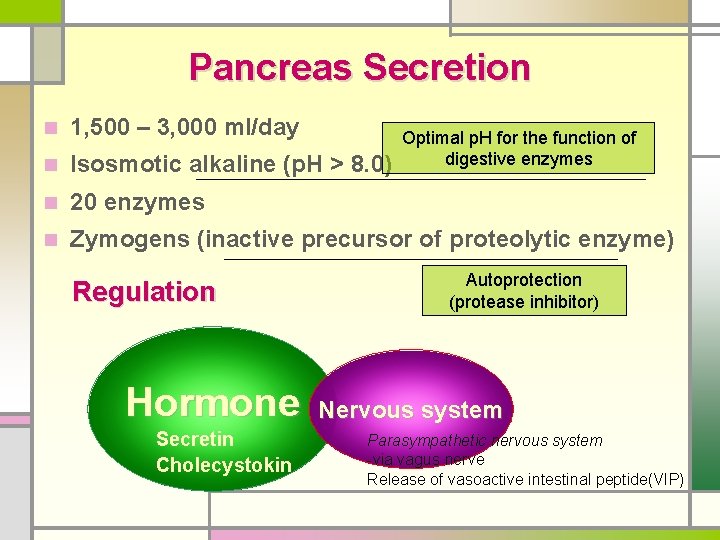

Pancreas Secretion n 1, 500 – 3, 000 ml/day n Isosmotic alkaline (p. H > 8. 0) n 20 enzymes n Zymogens (inactive precursor of proteolytic enzyme) Regulation Hormone Secretin Cholecystokin Optimal p. H for the function of digestive enzymes Autoprotection (protease inhibitor) Nervous system Parasympathetic nervous system -via vagus nerve Release of vasoactive intestinal peptide(VIP)